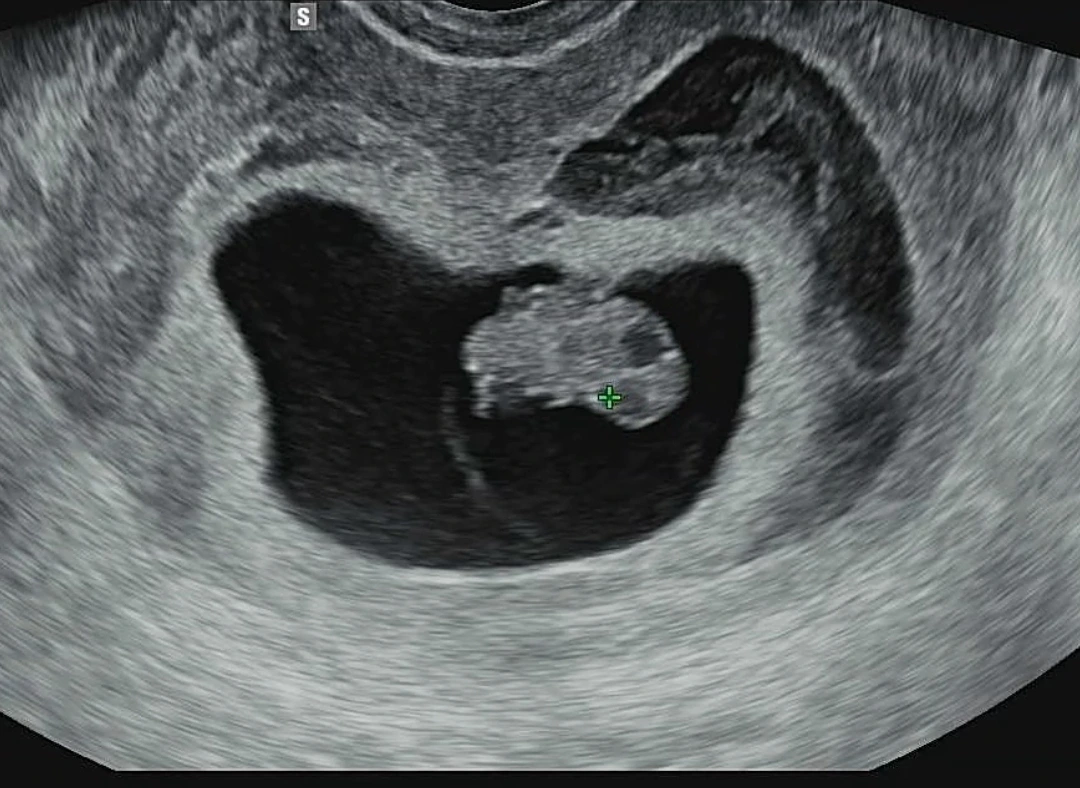

오늘 일주일 만에 병원진료를 다녀왔다. 그 사이 둘째, 일명 호랭이는 2cm의 귀여운 땅콩이 되어 있었다.

땅콩모양 아래로 짧게 돋아난 팔과 다리가 앙증 그 자체였다. 여전히 임신이 모든 게 새롭고, 아기의 성장도 매번 새롭다.

오늘 초음파 사진을 보고 나서야 둘째의 존재감이 약간 현실적으로 다가왔다. 그동안은 유산할지도 모른다는 걱정에 내 뱃속에 어엿한 한 생명이 크고 있다는 사실 자체를 잘 느끼지 못했는데, 조 작은 것이 이제 팔, 다리도 있다니... 장하고, 또 장했다.